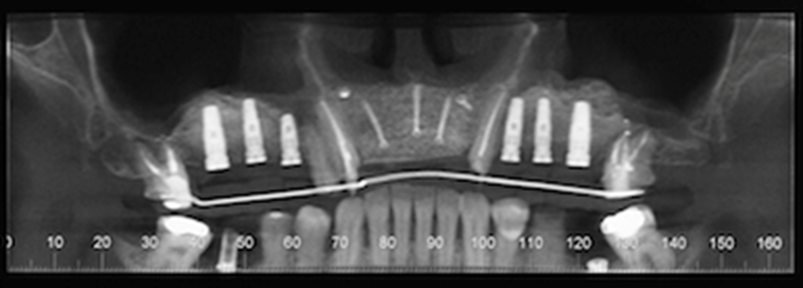

At the 8-months follow-up, a CBCT scan showed consolidation of the grafted material with the recipient bone (Figure 6). A second surgical procedure was conducted under local anesthesia and oral sedation in order to remove the titanium mesh. At this appointment, the pre-maxilla showed to be significantly augmented (Figure 7) with the dimension of 14 mm in height and 10 mm in width. The bone characteristics were soft, erythematous, with a cancellous texture. Four dental implants (Biomet 3I certain®, USA) were inserted, with no more than 25 Ncm2 of primary stability (Figure 8). The implants were uncovered 6 months later for initiation of the prosthetic rehabilitation using 4 single-unit crowns. One-year follow-up showed to be uneventful (Figure 9).

Figure 6.CBCT scan 8 months post ridge augmentation. Note significant increase in bone augmentation of the pre-maxilla. Presence of implants for sites #2, 3, 4, 11, 12 and 13 after right and left sinus lifts were performed.